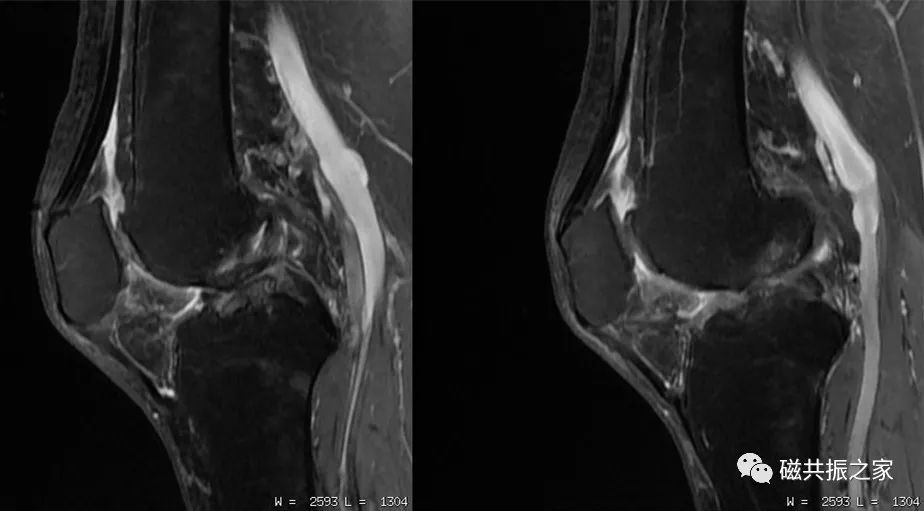

如图,上1,2幅图像为带宽12.5kHz;下1,2幅图像为带宽31.2kHz,(GE机型);虽然上两幅图像的信噪比比下两幅图像更高,但其分辨率明显不及带宽为31.2kHz的图像。

如在四肢关节扫描中,回波链设置过长(图中回波链为16),采集的时间跨度过大,会导致图像的模糊伪影,锐利度降低,细节分辨不清。所以应根据实际的需求合理设置回波的长度。

缩短回波链(图中回波链为8),通常为6-10,不仅能更好的显示一些细微结构,也能使得关节软骨的信号更高。特别是在四肢小关节的扫描中,宁可减小采集(激励)次数,也不要轻易的增加回波链长度。同时,需要说明的是回波链也不是越短越好。